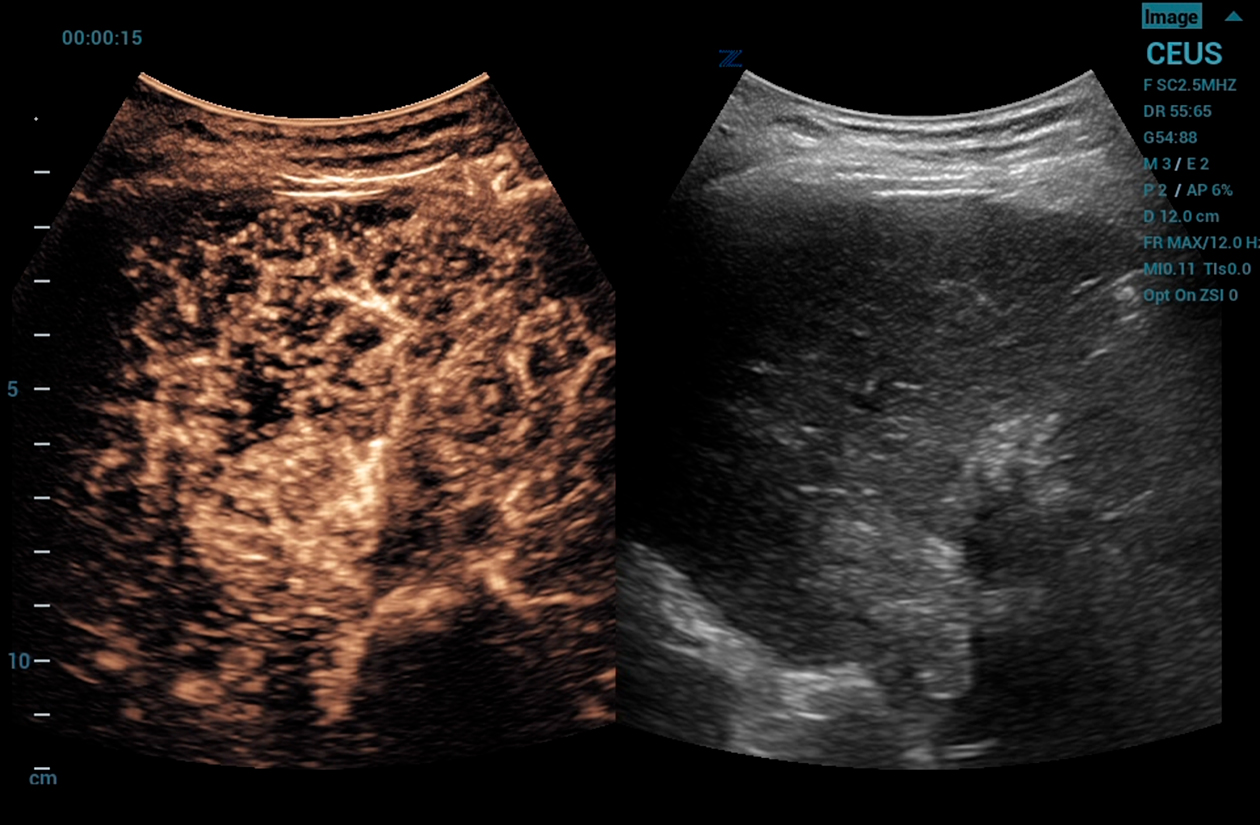

CEUS

Contrast Enhanced Ultrasound (CEUS), Mindray’s unique approach to contrast imaging, allows clinicians to obtain the information needed with a lower dose of the contrast agent. CEUS is now available on all imaging transducers (1-20MHz).